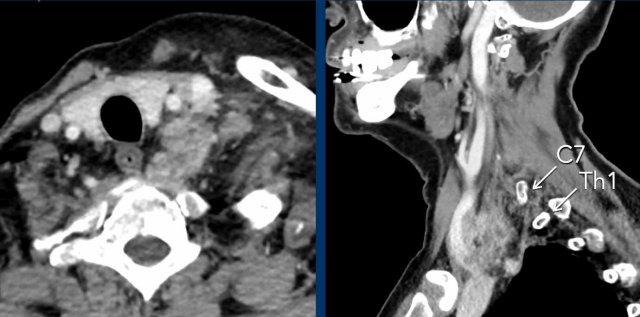

Bệnh nhân nam trẻ tuổi bị tai nạn khi tham gia đua xe mô tô địa hình.

Bệnh nhân được nhập vào khoa ICU với nhiều chấn thương.

Sau ba ngày, bệnh nhân hồi phục ý thức và được ghi nhận có liệt nửa người bên phải, không thể giải thích bằng bất kỳ tổn thương não nào.

Bệnh nhân cũng có hội chứng Horner bên phải.

Hình ảnh

CT lúc nhập viện cho thấy gãy mỏm ngang C7 và gãy xương sườn thứ nhất (đầu mũi tên).

Trên CECT có hiện tượng thoát thuốc cản quang cho thấy đang chảy máu tích cực (vòng tròn).

Continue with the MRI…

Đầu tiên, siêu âm vùng cổ được thực hiện để tìm kiếm tổn thương đứt rễ thần kinh, tuy nhiên việc khảo sát này bị hạn chế do các thay đổi chấn thương ở vùng này.

Sau đó, chụp MRI được thực hiện.

Hình ảnh cắt ngang cho thấy sự tăng cường tín hiệu của các rễ thần kinh, gợi ý tổn thương đám rối thần kinh cánh tay.

Cũng lưu ý tổn thương phần mềm cạnh cột sống bên phải.

Continue….

Ngoài ra, hình ảnh T2W cho thấy một số tín hiệu cao nhẹ trong tủy sống bên phải (mũi tên).

Điều này được xem là bệnh lý tủy sống sau chấn thương và cũng có thể là giải thích cho hội chứng Horner bên phải.